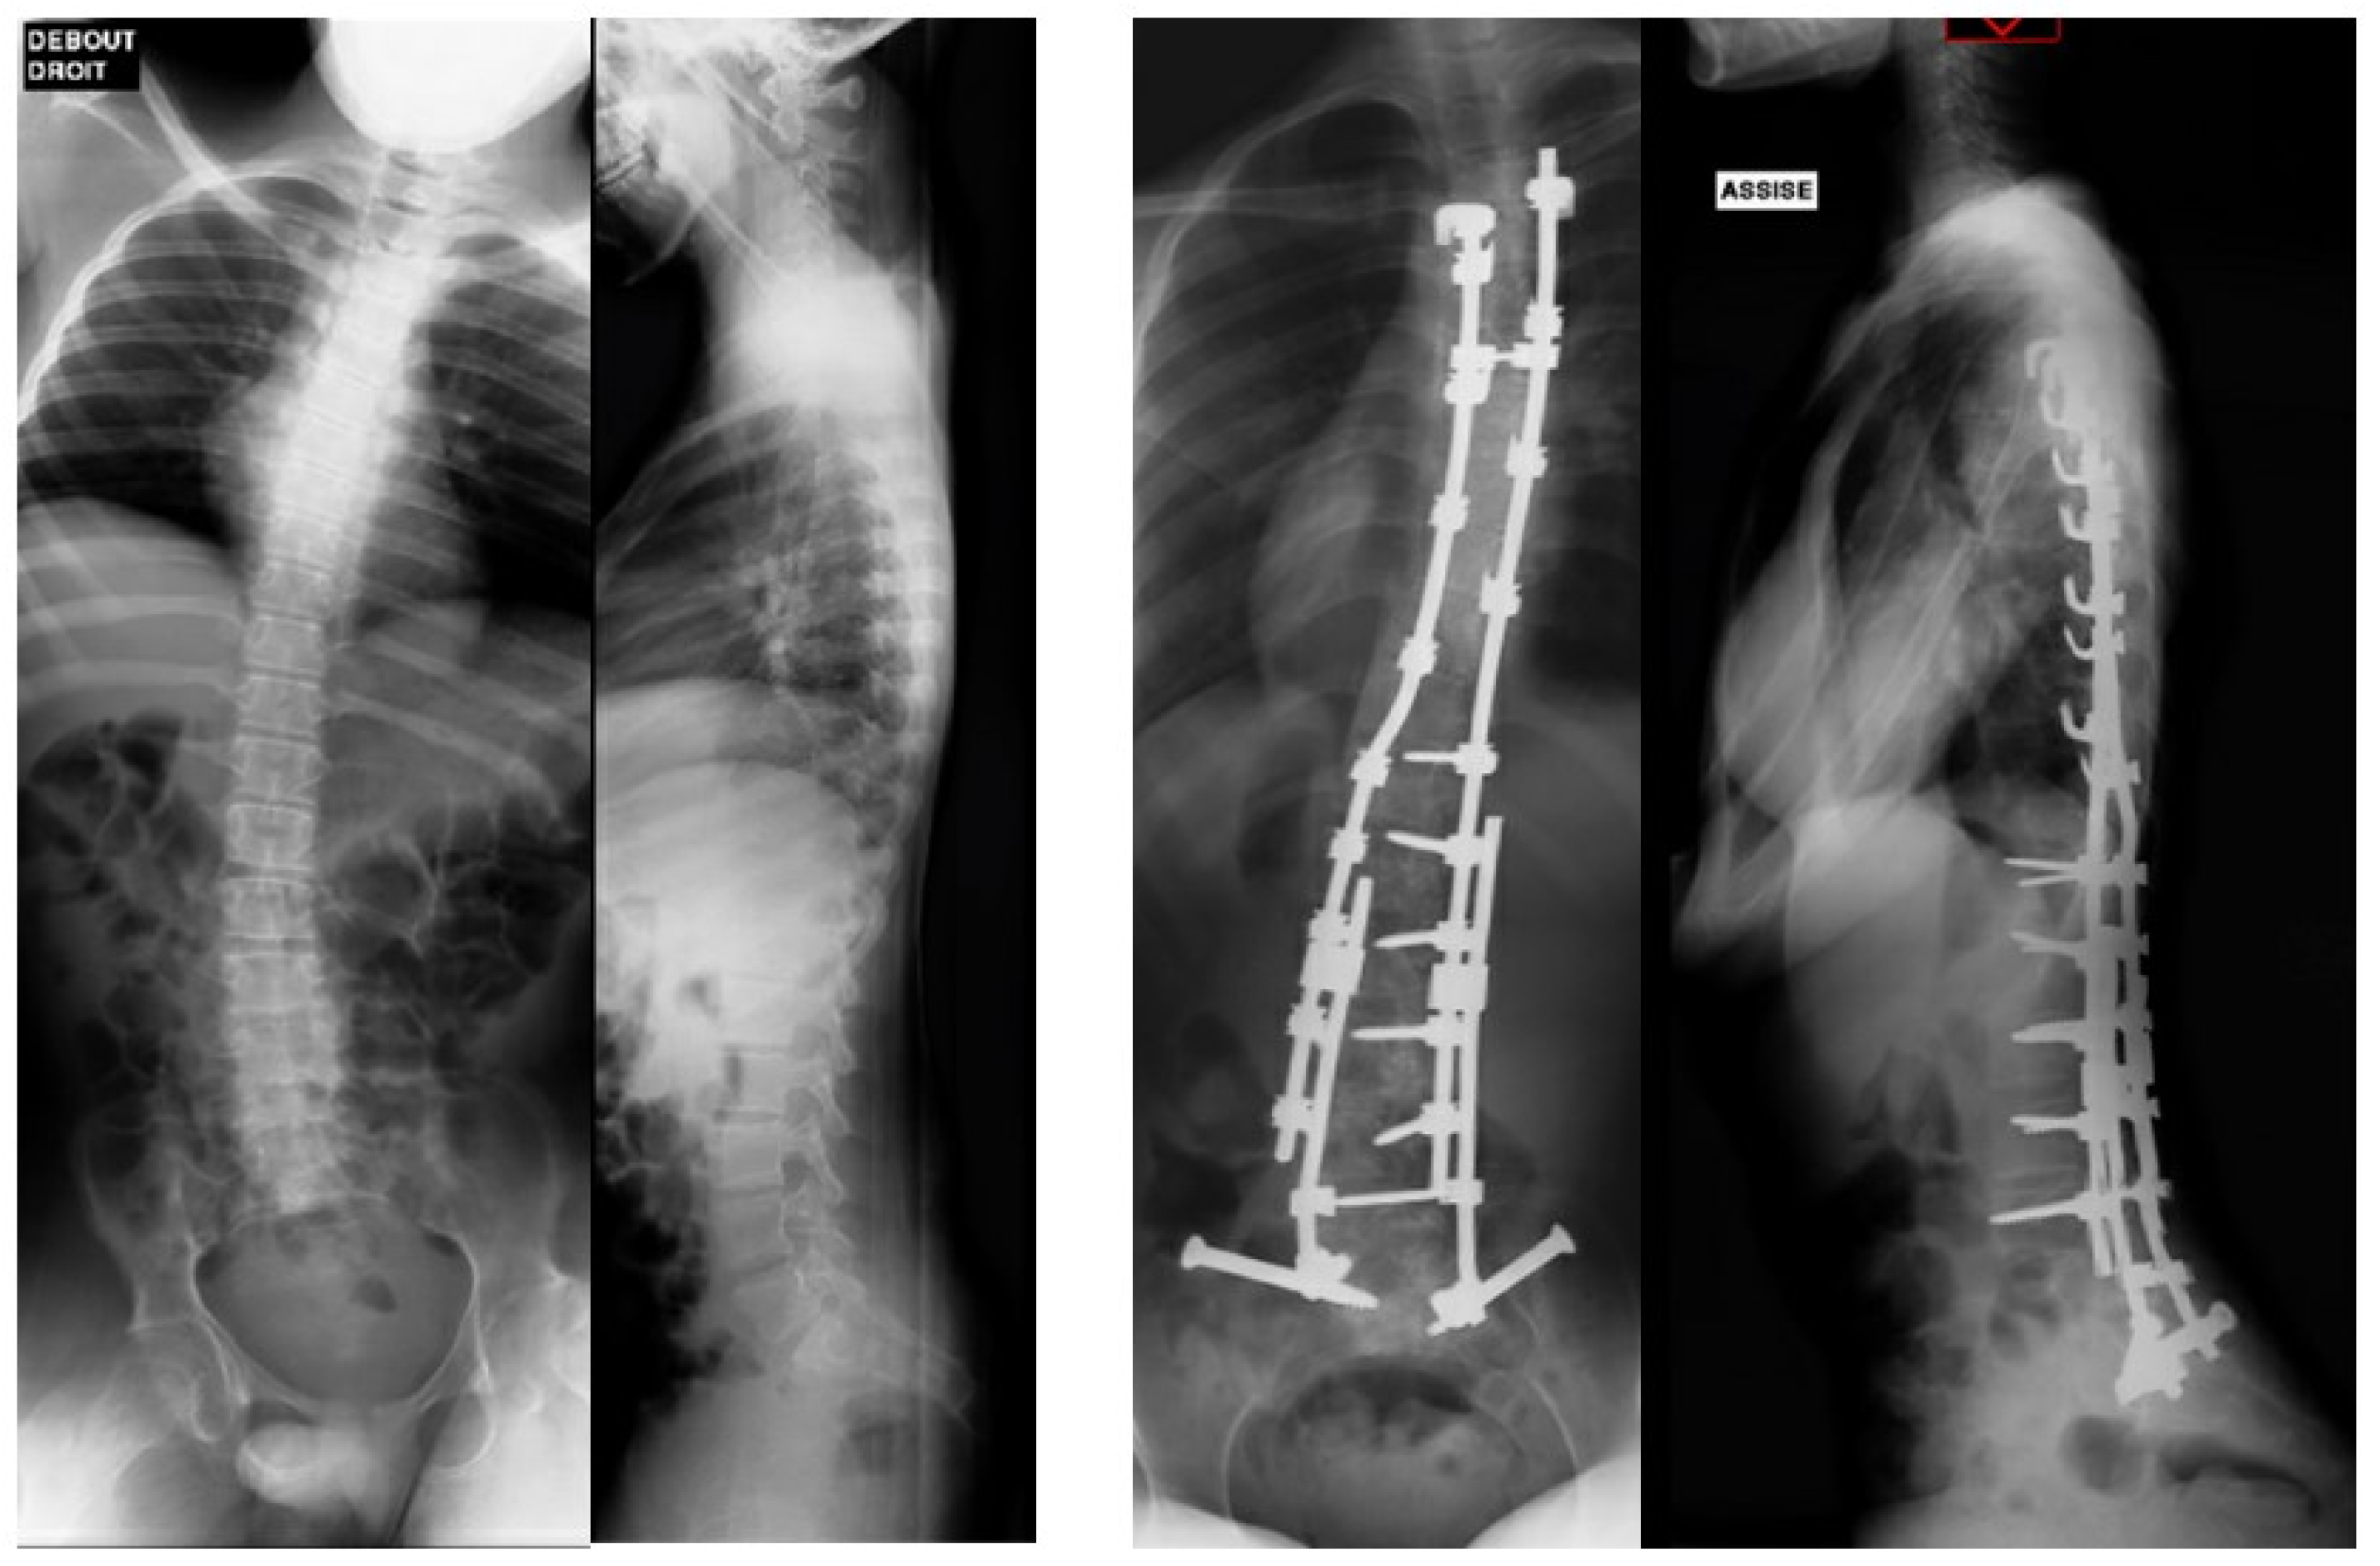

| Preoperative pelvic obliquity, (°), mean | 23 | 23 | 23 | |

| Last FU pelvic obliquity improvement (°), mean | −10.2 (44%) | −17.8 (77%) | −14 | |

| Preoperative Cobb angle, (°), mean | 50.5 | 77 | 63.8 | |

| Last FU Cobb correction improvement, (°), mean | −31.1 (61%) | −47.8 (62%) | −39.5 | |

| Loss of frontal or sagittal correction | None | None | None | |

| Sitting posture and comfort improvement | All cases | All cases | All cases |